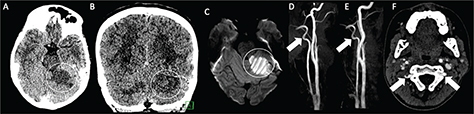

Fig 1

Figure 1. A six-month-old male who presented with acute right hemiparesis. DWI (A) demonstrates acute infarct in the left basal ganglia and deep white matter (white arrow). MRA (B) shows severe stenosis of the left M1 middle cerebral artery segment (black arrow). Follow-up 4 months later, demonstrates evolution of the infarct, now with encephalomalacia and gliosis without new acute infarct (white arrowhead) (C). MRA at that times shows mild improvement but persistent MCA stenosis (black arrowhead) (D). Findings are most compatible with focal cerebral arteriopathy.